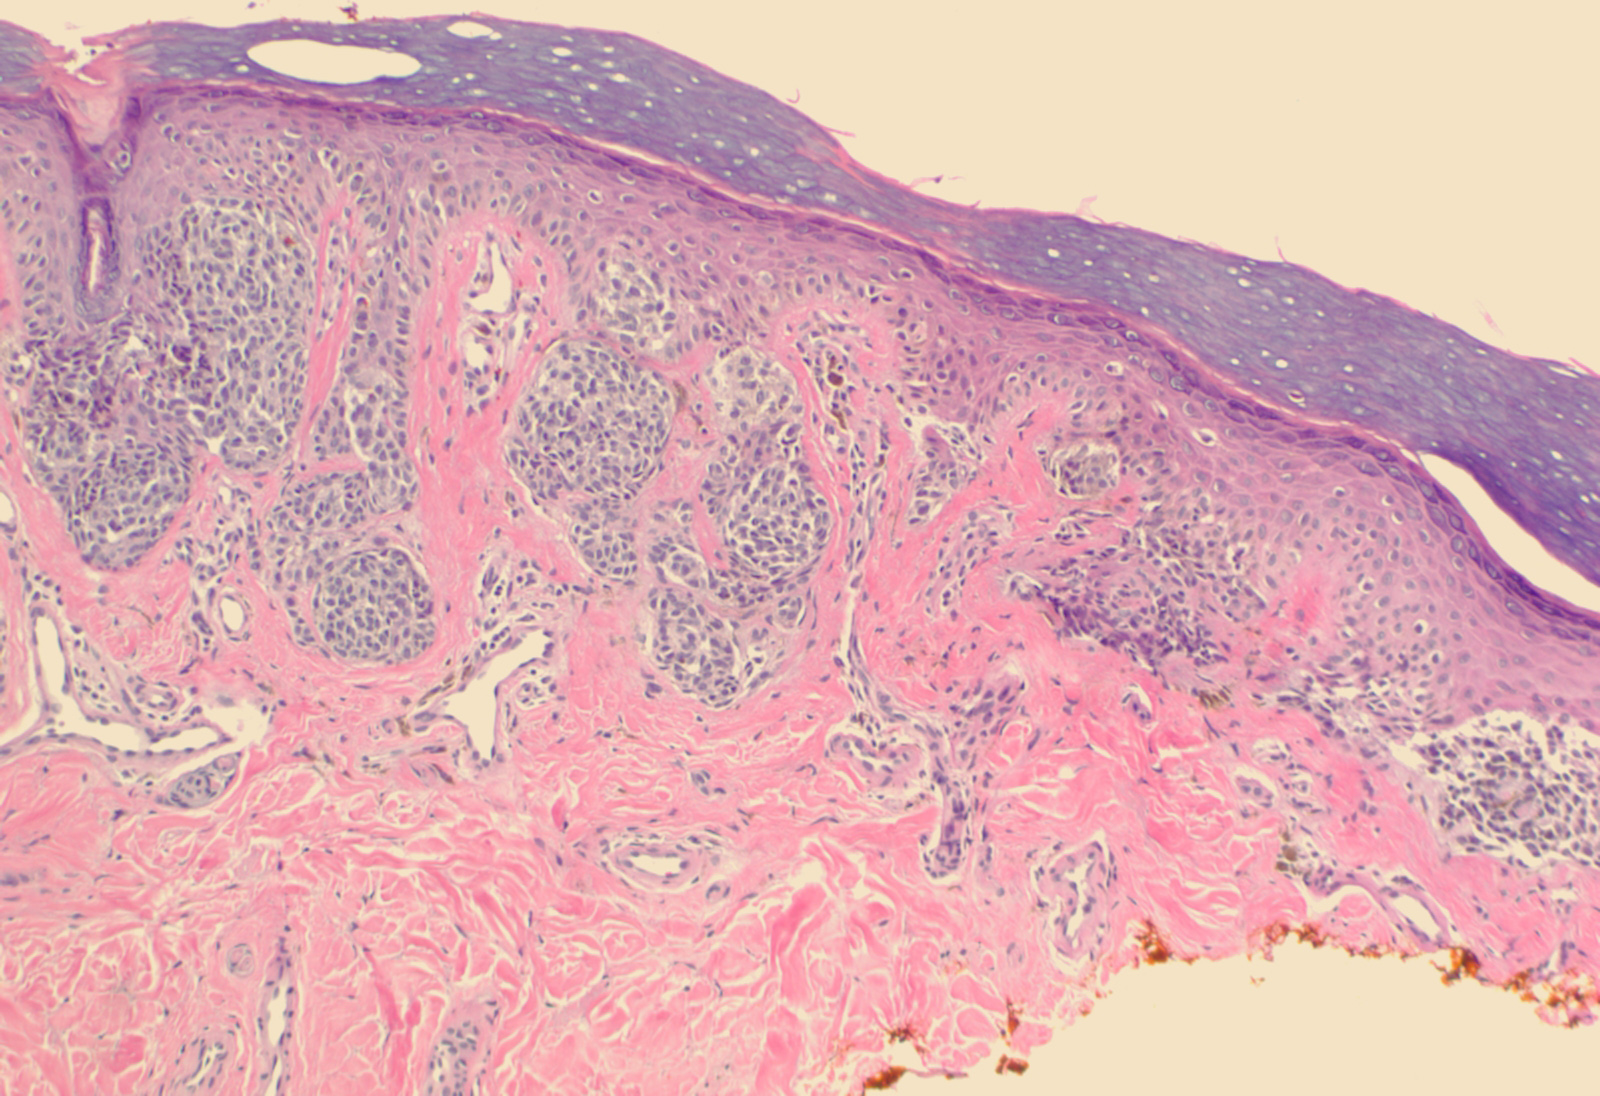

Acral nevus =وحمة النهايات